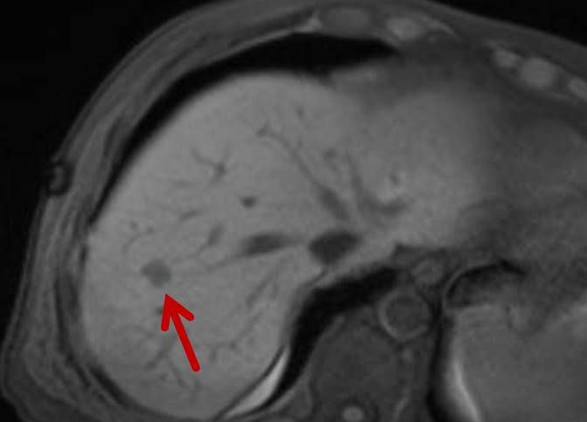

Präoperative Tumormarkierung

Eine Voraussetzung für die vollständige chirurgische Entfernung von Knochen- und Weichteiltumoren ist die präzise Erkennung der Tumorausdehnung und der Tumorgrenzen. Mit der Kernspintomographie (MRT) kann das Tumorgewebe exzellent von gesundem Gewebe abgegrenzt werden und somit die Ausdehnung vor der Operation bestimmt werden. Nach der kernspintomographischen Bestimmung der Tumorausdehnung werden unter kontinuierlicher MRT-Bildgebung die Grenzen des Tumors markiert. Die Marker werden mit einer Nadel ins angrenzende gesunde Gewebe eingebracht. Die Markierung kann am Tage vor der Operation durchgeführt werden. Alternativ ist die Tumormarkierung auch mit anderen bildgebenden Verfahren möglich, z.B. mit der Computertomographie oder dem Ultraschall.

Abbildung: Bei diesem Patienten wurde ein im Röntgen nur schlecht sichtbarer Knochentumor vor der Operation unter MRT-Kontrolle mit kleinen röntgendichten Spiralen („Coils“) markiert. Damit hat der Operateur eine optimale Darstellung des Tumorbereichs bzw. der Tumorgrenzen und kann gezielter, schonender und effektiver operieren.